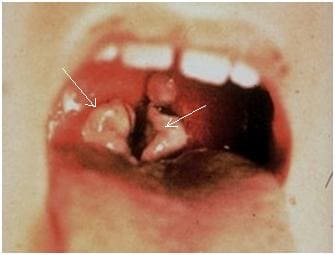

Паратонзиллит и паратонзиллярный абсцесс это две фазы одного и того же процесса, вначале возникает воспаление тканей около миндалины – паратонзиллит, затем происходит их гнойное расплавление - формируется абсцесс. Эти осложнения возникают спустя 2-3 дня после ангины. Появляется боль при глотании больше с одной стороны, резко повышается температура. Открывание рта затруднено, отмечается повышенное слюноотделение. Характерно положение головы больного: для того, чтобы уменьшить напряжение пораженных тканей, он наклоняет ее в больную сторону. При осмотре глотки отмечается выраженная асимметрия: пораженная миндалина напряжена и смещается к центру, мягкое небо отечно, язычок смещен в сторону.

Хочется собрать воедино признаки и симптомы, которые должны заставить человека немедленно обратиться к врачу: